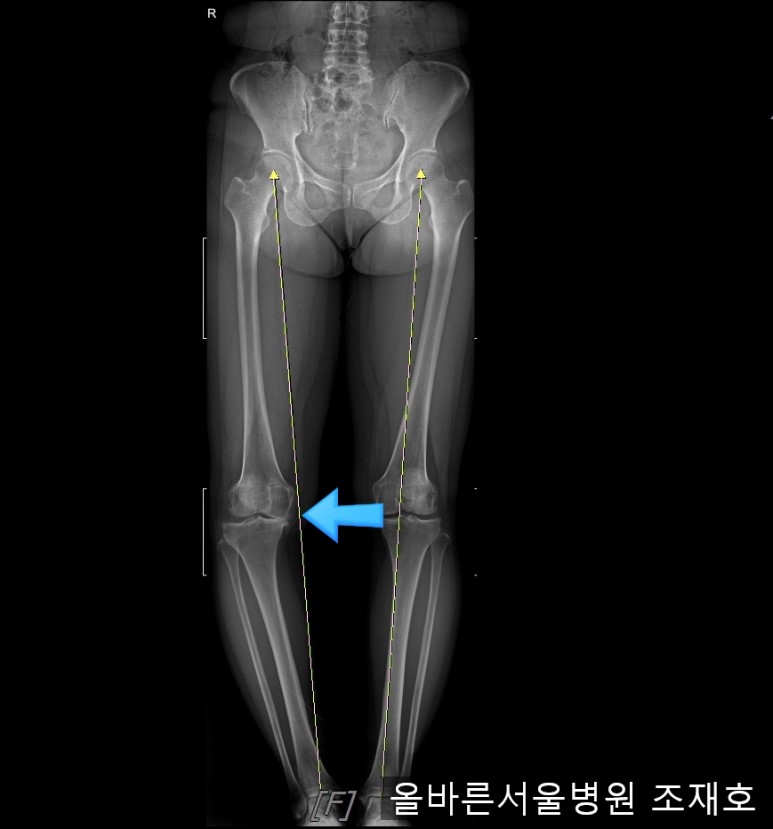

观察膝盖下肢排列的扫描图像可看到右腿严重变形,身体中心向内倾斜。

这种状态下原本打算在其他医院做人工关节置换,后又到我院接受治疗。